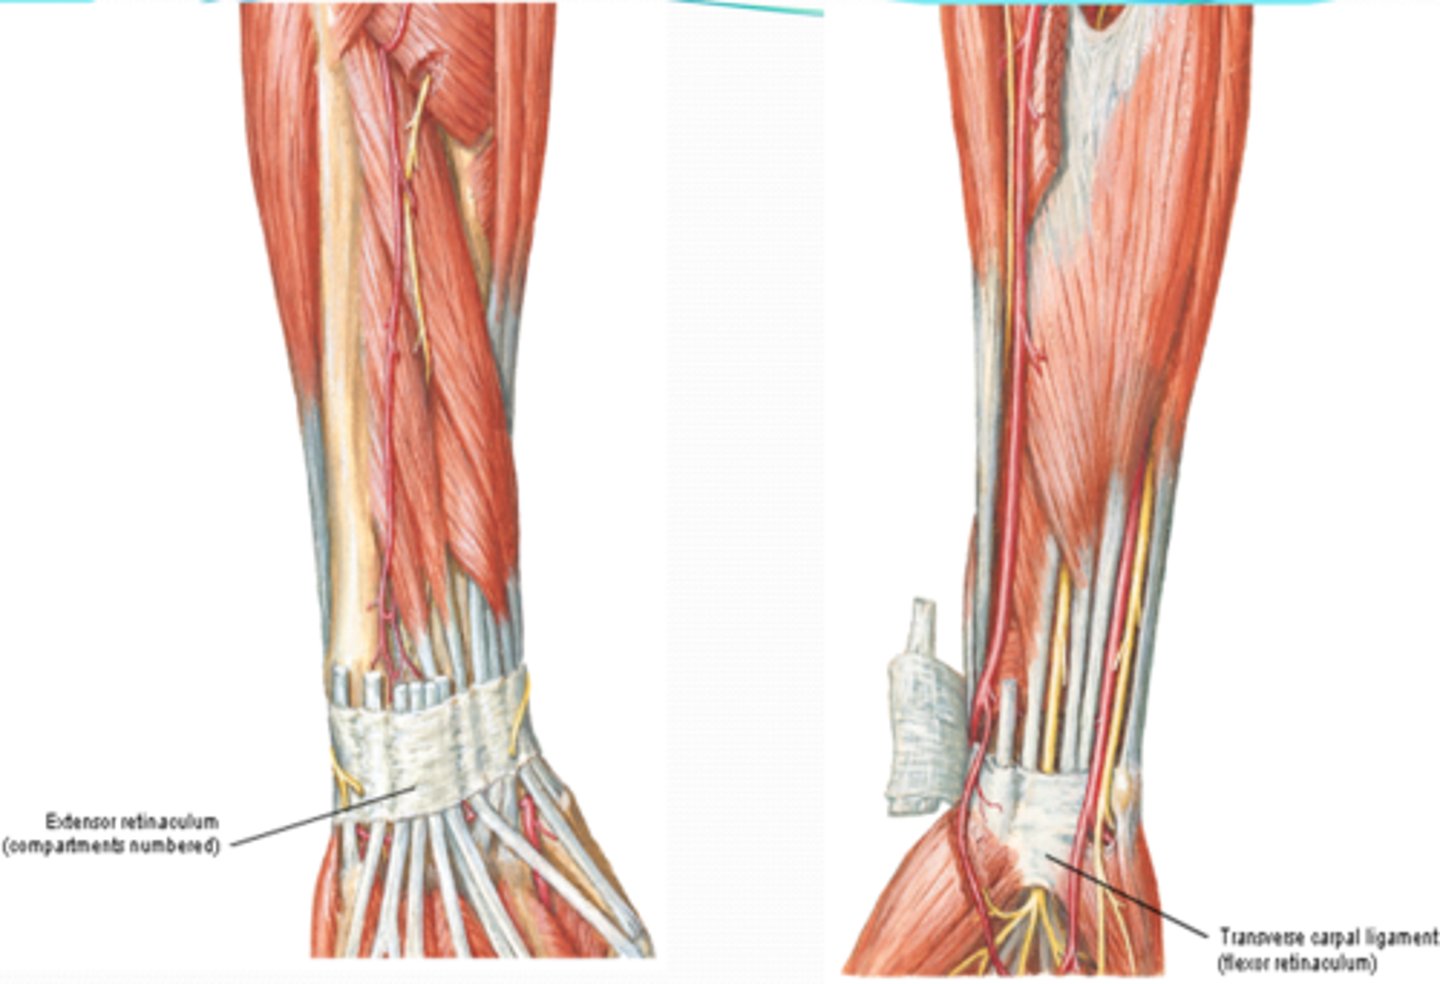

(Antebrachial fascia:) Transverse bands

-Extensor retinaculum

-Flexor retinaculum (transverse carpal ligament)

-Palmar carpal ligament

(Antebrachial fascia's Transverse bands:) Extensor retinaculum

in the posterior region, retains extensor tendons in place

(Antebrachial fascia's Transverse bands:) Flexor retinaculum (transverse carpal ligament)

forms the roof of the carpal tunnel, which contains flexor tendons and the median nerve

(Antebrachial fascia's Transverse bands:) Palmar carpal ligament:

in the anterior region superficial to the flexor retinaculum, and continuous with the extensor retinaculum in the posterior region